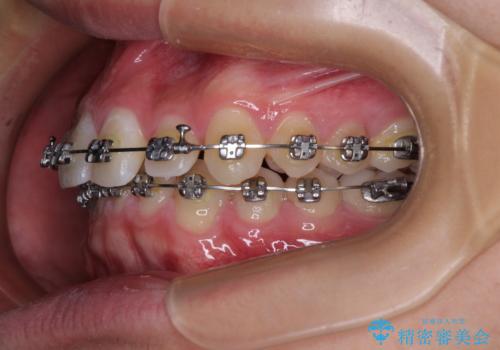

- メタルブラケット

- 1年1ヶ月

ワイヤー矯正でもインビザライン矯正でも対応可能でしたが、インビザラインでの自己管理の煩わしさを避けるため、ワイヤー装置にて矯正治療を行うこととしました。

傾斜しいている大臼歯を立ち上げながら、下顎歯列を上顎に対して前方位となるように工夫し、デコボコを解消した上でディープバイトも改善することができました。